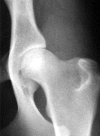

classificazione grado aGrado A: nessun segno di displasia dell'anca (HD 0 / HD -). La testa del femore e l'acetabolo sono congruenti. Il bordo craniolaterale appare netto e leggermente arrotondato. Lo spazio articolare risulta netto ed uniforme. L'angolo acetabolare secondo Norberg è di circa 105° o superiore. Quando inoltre il bordo craniolaterale circonda leggermente la testa del femore in direzione laterocaudale, la conformazione articolare viene definita "eccellente" (A1).

classificazione grado bGrado B: articolazione dell'anca quasi normale (HD 1 / HD +/-). La testa del femore e l'acetabolo appaiono leggermente incongruenti e l'angolo acetabolare secondo Norberg è di circa 105° oppure il centro della testa del femore si trova medialmente al bordo acetabolare dorsale con congruità della testa del femore e dell'acetabolo.

classificazione grado cGrado C: leggera displasia dell'anca (HD 2 / HD +). La testa del femore e l'acetabolo appaiono incongruenti, l'angolo acetabolare secondo Norberg è di circa 100° e/o il bordo cranio laterale risulta appiattito. Possono essere presenti irregolarità o segni minori di modificazioni osteoartrosiche a carico del margine acetabolare craniale, caudale o dorsale o della testa e del collo del femore.

classificazione grado dGrado D: media displasia dell'anca (HD 3 / HD ++). Incongruità evidente tra la testa del femore e l'acetabolo con sublussazione. L'angolo acetabolare secondo Norberg è superiore a 90°. Saranno presenti un appiattimento del bordo craniolaterale e/o segni di osteoartrosi.

classificazione grado eGrado E: grave displasia dell'anca (HD 4 / HD +++). Sono presenti modificazioni marcate di tipo displastico delle anche, come lussazione o sublussazione distinta, un angolo acetabolare secondo Norberg inferiore a 90°, un evidente appiattimento del marg ine acetabolare craniale e deformazione della testa del femore (a forma di fungo o appiattita) o la presenza di altri segni di osteoartrosi.